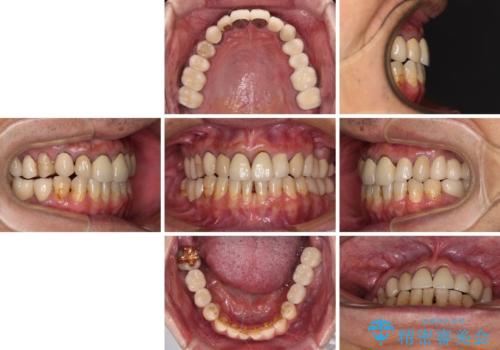

奥歯1歯分を動かすには時間がかかるため、矯正治療には思いの外時間がかかりました。

痛みのある奥歯は必要に応じて根管治療を行い、左下インプラントは角化歯肉の移植により清掃性を向上させ、気になっていた部分をしっかりと改善させることができました。